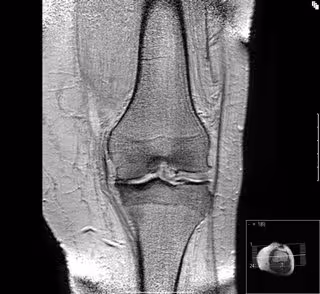

Artrosis de rodilla

La artrosis es la más común de las enfermedades articulares y constituye una de las principales causas de consulta para el médico de familia. Es una enfermedad degenerativa que se produce al alterarse las propiedades mecánicas del cartílago y que se acompaña de afectación de otras estructuras de la articulación como son el hueso subcondral, la cápsula articular y la membrana sinovial, entre otras.

La prevalencia de la artrosis aumenta con la edad, aunque los datos son muy variables dependiendo si se atiende solamente a la aparición de signos radiológicos o bien a la existencia de síntomas de la enfermedad. Constituye la causa más importante de discapacidad entre los ancianos en España y en otros países del mundo occidental. Su prevalencia en España en los mayores de 20 años, según el estudio de prevalencia de enfermedades reumáticas en la población española, es de un 10,2% en la rodilla, alcanzando hasta 30% en mayores de 60 años.